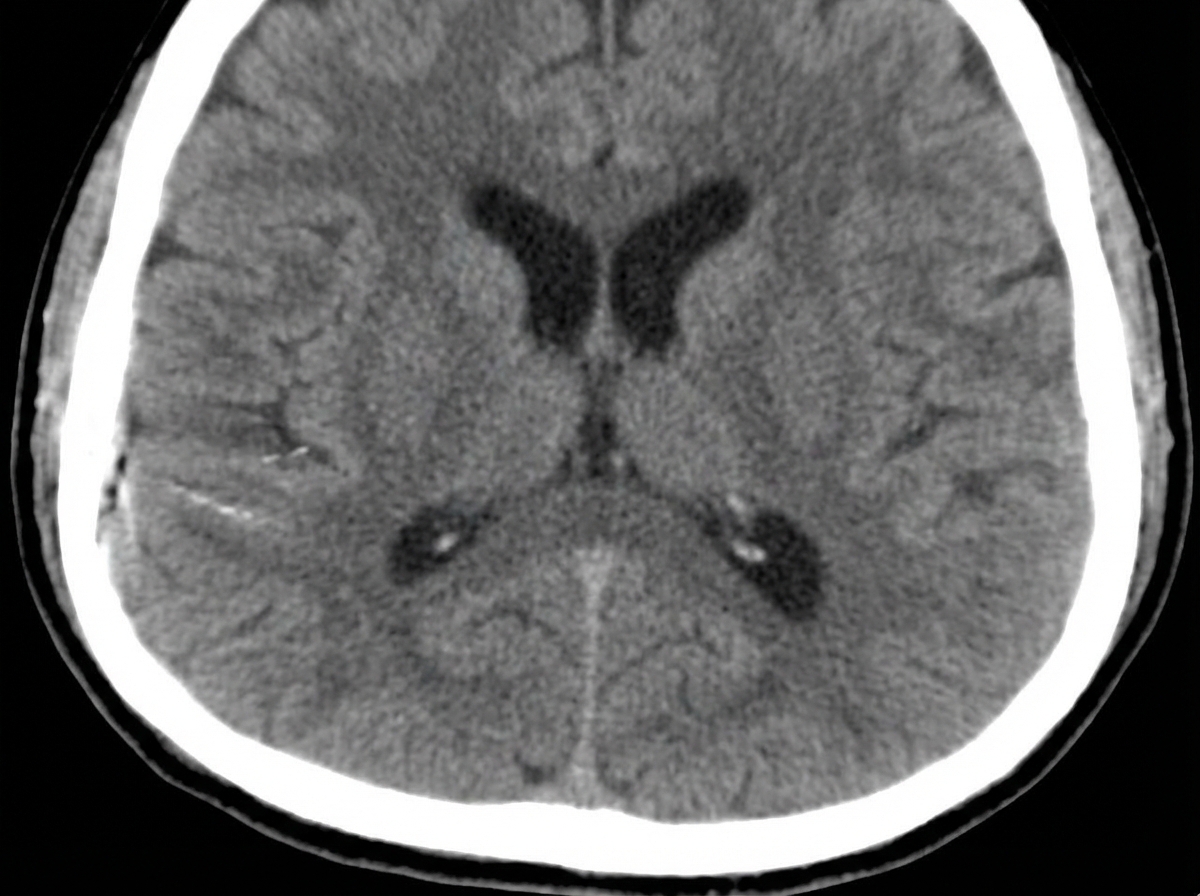

A 31-year-old unresponsive man is admitted to the emergency department after a single-vehicle roll-over accident. On primary assessment by paramedics, he was unresponsive. On admission, he opened his eyes to painful stimuli, was not responsive to verbal commands, and demonstrated abnormal flexion of his arms with extension of his legs in response to pain. The patient was intubated and examined. The blood pressure is 150/90 mm Hg; the heart rate, 56/min; the respiratory rate, 14/min; the temperature, 37.5℃ (99.5℉), and the SpO2, 94% on room air. The examination shows a depressed fracture of the left temporal bone and ecchymoses and scratches over his abdomen and extremities. His pupils are round, equal, and show a poor response to light. There is no disconjugate eye deviation. His lungs are clear to auscultation and the heart sounds are normal. Abdominal examination reveals normal bowel sounds and no fluid wave. There are no meningeal signs. Focused assessment with sonography for trauma is negative for blood in the abdominal cavity. Head CT scan is shown in the picture. Which procedure is required to guide further management?